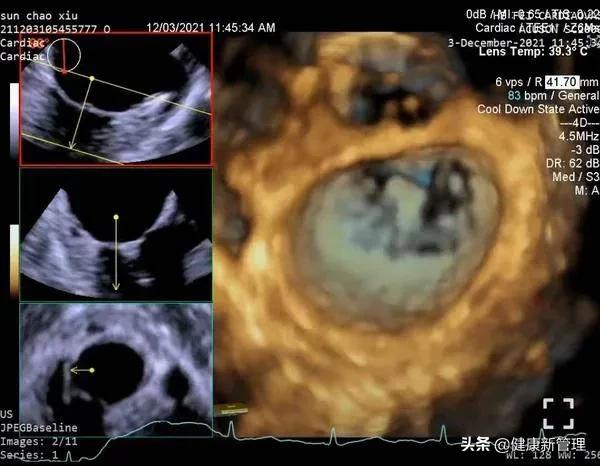

术前心脏彩超完善各项术前准备后,患者于全麻下,梅举教授主刀,经食道超声引导,经心尖送入二尖瓣夹,捕获并夹合二尖瓣前后叶病变处,二尖瓣夹位置稳定。术后超声显示,该患者二尖瓣反流即刻减少。

二尖瓣夹系统植入术后